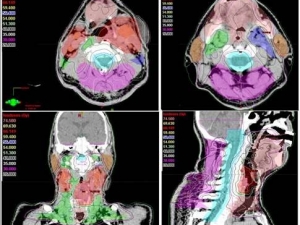

Kanser Tedavisinde ’Yapay Zeka’ Başarısı